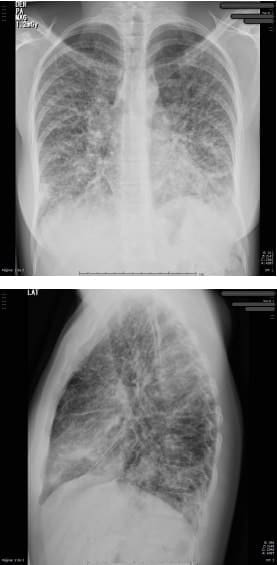

En la radiografía de tórax de control (figura 4) se aprecian cambios dados por opacidades reticulares bilaterales en 4 cuadrantes y aumento del proceso reticular previo, por lo que se hace necesario la toma de biopsia pulmonar por parte de cirugía de tórax.

Figura 4. Radiografía de tórax proyección AP y lateral con

opacidades reticulares bilaterales en 4 cuadrantes.